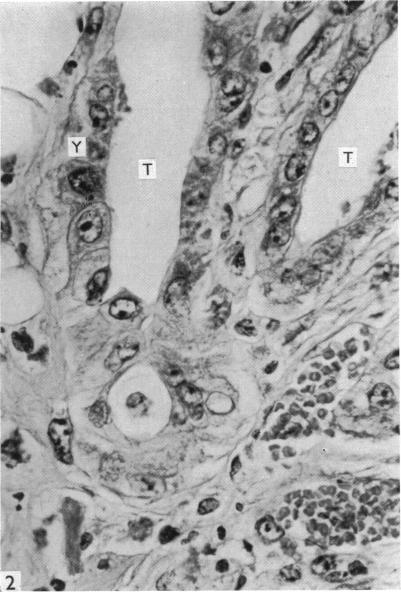

As a contribution to the problem of the immunological privilege of the fetus it was decided to investigate the fate of yolk sac grafts in mice. Ten-day post-coitum mouse visceral yolk sac was transplanted to a dermal tunnel in the flank of isogeneic animals. In this site the yolk sac was capable of surviving for at least 15 days past the normal duration of pregnancy. Yolk sac was transplanted to a similar site in allogeneic animals and was found to be destroyed by an immunological reaction within 13 days. Orthotopic skin grafts between the same strains of mice used in the yolk sac transplantation were rejected in first-set fashion within 13 days. A limited series of host animals, previously sensitized by visceral yolk sac, rejected orthotopic skin grafts in second-set fashion. These findings indicate that the cells of the visceral yolk sac in the mouse contain transplantation antigens. Possible reasons why such antigens do not lead to fetal rejection during pregnancy are considered.

为了研究胎儿免疫特权问题,决定对小鼠卵黄囊移植的命运进行研究。将受孕10天的小鼠内脏卵黄囊移植到同基因动物胁腹的皮肤隧道中。在此部位,卵黄囊能够在超过正常孕期的时间内存活至少15天。将卵黄囊移植到异基因动物的类似部位,发现其在13天内被免疫反应破坏。在卵黄囊移植中使用的相同品系小鼠之间的原位皮肤移植在13天内以初次排斥的方式被排斥。一系列有限的先前经内脏卵黄囊致敏的宿主动物以二次排斥的方式排斥原位皮肤移植。这些发现表明,小鼠内脏卵黄囊的细胞含有移植抗原。文中还考虑了此类抗原在孕期为何不会导致胎儿被排斥的可能原因。